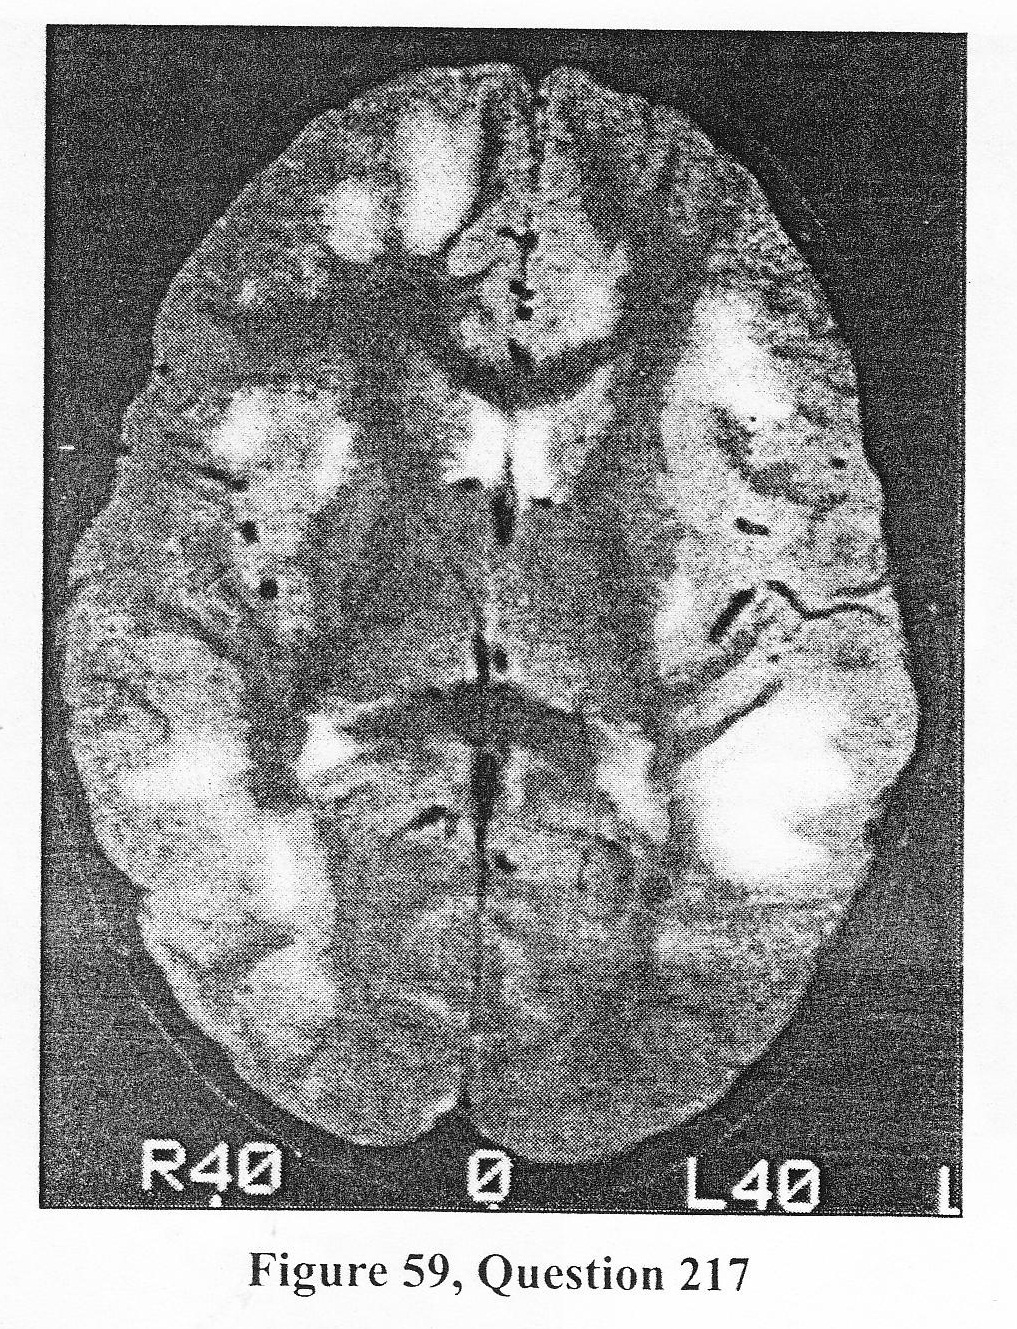

A 12-year-old girl has had sudden onset of weakness punctuated by partial seizures with secondary generalization. She has had normal development and has been healthy all of her life, although her parents note that she had a fever and pharyngitis about Wi weeks prior to the onset of the current illness. The physical exam reveals a stuporous child with spastic quadriparesis and right seventh cranial nerve palsy. Analysis of CSF reveals 55 white cells, all lymphocytes and monocytes, and 3 red cells. The protein is slightly elevated but the glucose is normal. An MR was obtained and is depicted in Figure 59. 217. The MOST LIKELY diagnosis is:

B. acute disseminated encephalomyelitis